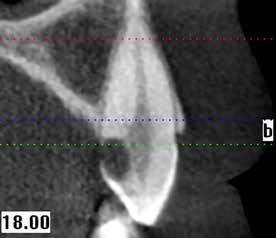

A maradó fogak gyökérreszorpciója patológiás folyamat. Az elváltozások elhelyezkedése alapján csoportosíthatjuk őket külső és belső reszorpciós folyamatokra. A külső gyökérreszorpciók egyre gyakrabban diagnosztizált formája a külső nyaki reszorpció (angolul External Cervical Resorption, ECR) [1. és 2. kép]. Az ECR egy komplex elváltozás, amely egyszerre érintheti a fog keményszöveti állományát, a parodontális szöveteket és előrehaladott esetben a pulpaszövetet is. A modern diagnosztikai eszközöknek köszönhetően egyre gyakrabban és egyre korábban kerül diagnosztizálásra ez a típusú lézió, így a kezelése is egyre inkább a mindennapi klinikum részévé válik az endodonciával foglalkozó kollégák számára. A 3 dimenziós diagnosztikai eszközök terjedésével felmerült az igény egy 3 dimenziós klasszifikációra. Patel és munkatársai 2018-ban kidolgoztak egy új klasszifikációt, amely segít az elváltozások kategorizálásában és a kezelések tervezésében [1]. A téma aktualitását jól mutatja, hogy ezzel egy időben az ESE (European Society of Endodontology) is kidolgozott egy állásfoglalást a külső nyaki reszorpciók diagnosztikájával és terápiás lehetőségeivel kapcsolatban [2].

Ötvenes éveiben járó páciensünk rutinellenőrzésre érkezett rendelőnkbe. A vizsgálat során felfigyeltünk a jobb felső metszőfogán kialakult, íny alatti elváltozásra. A röntgenfelvételen jól látható a kis méretű (Patel 1Ad) reszorpciós elváltozás [3. kép]

1. és 2. kép: Külső nyaki reszorpciós elváltozások CBCT képen.9. kép: Referáló orvos által készített röntgenfelvétel – 10. kép: CBCT felvételen 3 dimenzióban értékelhető a reszorpciós kavitás kiterjedése.